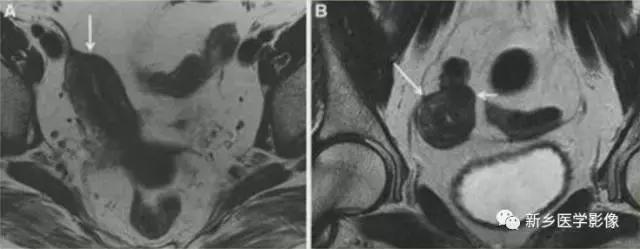

V:纵隔子宫

左图:完全纵隔子宫,纵隔延伸至宫颈内口。

中图:部分纵隔子宫,纵隔未达宫颈内口。

纵隔子宫:宫底轮廓凸出、平坦、轻度凹陷<1cm,肌壁或纵隔深入内膜腔>1cm。

弓形子宫:宫底轮廓凸出、平坦、轻度凹陷<1cm,肌壁或纵隔深入内膜腔<1cm。

完全型纵隔子宫:短T2信号纵隔贯穿宫腔,宫颈管及阴道上段。

MR诊断为完全型纵隔子宫伴阴道纵隔。

完全型纵隔子宫:宫底平坦,纵隔贯穿宫腔和宫颈

不完全型纵隔子宫:宫底平坦,纵隔未达宫颈内口水平